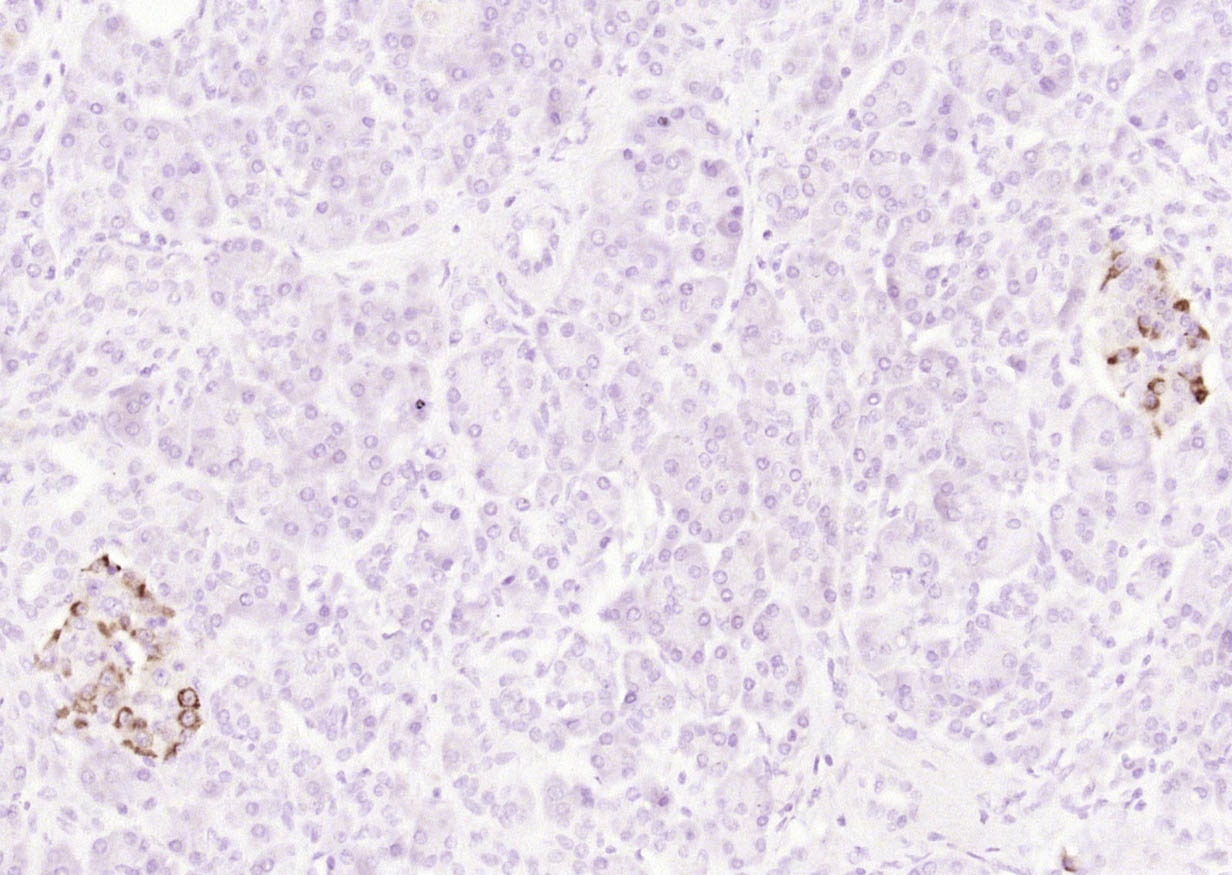

產(chǎn)品圖片

Paraformaldehyde-fixed, paraffin embedded (human pancreatic cancer); Antigen retrieval by boiling in sodium citrate buffer (pH6.0) for 15min; Block endogenous peroxidase by 3% hydrogen peroxide for 20 minutes; Blocking buffer (normal goat serum) at 37°C for 30min; Antibody incubation with (CD151) Polyclonal Antibody, Unconjugated (bs-22291R) at 1:200 overnight at 4°C, followed by operating according to SP Kit(Rabbit) (sp-0023) instructionsand DAB staining.